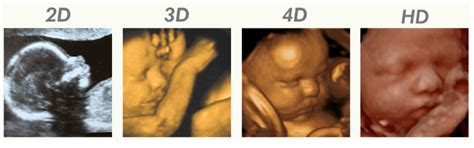

- 2D echo: De klassieke zwart-wit echo voor een profielbeeld.

- 3D/4D echo: Een gedetailleerde weergave van de baby in beweging.